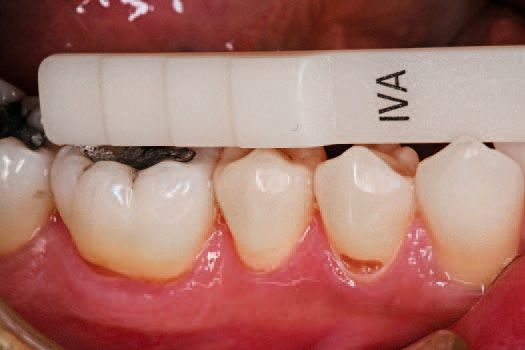

One of the three universal shades most closely matching the patient’s dentition was selected (Fig. 1). This patient was well matched to shade IVA (for slightly reddish teeth).